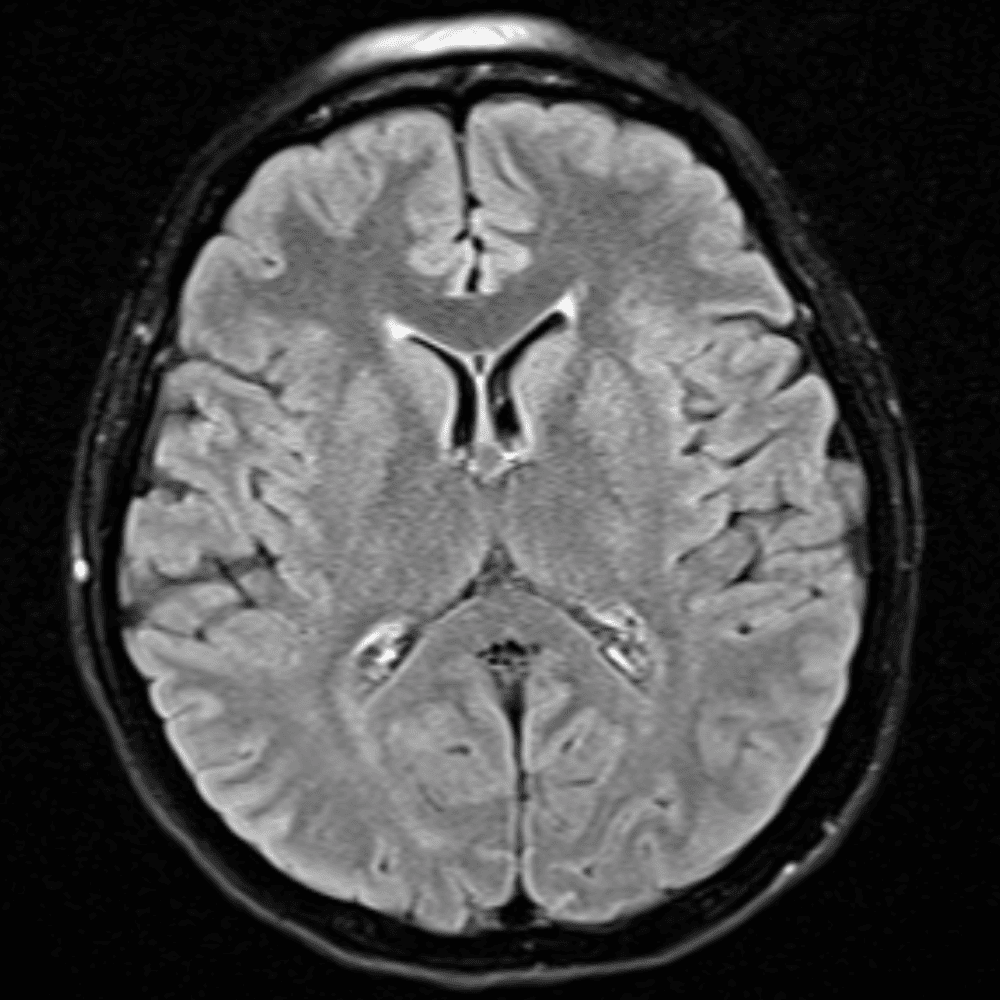

๋ฏธ๋ฌ˜ํ•˜๊ฑฐ๋‚˜ ์–ด๋ ค์šด ์‚ฌ๋ก€์™€ ์ผ๋ถ€ ์ •์ƒ ์‚ฌ๋ก€๋ฅผ ํฌํ•จํ•˜์—ฌ ๋‹น์ง์„ ์‹œ๋ฎฌ๋ ˆ์ด์…˜ํ•ฉ๋‹ˆ๋‹ค.

50 ์‚ฌ๋ก€